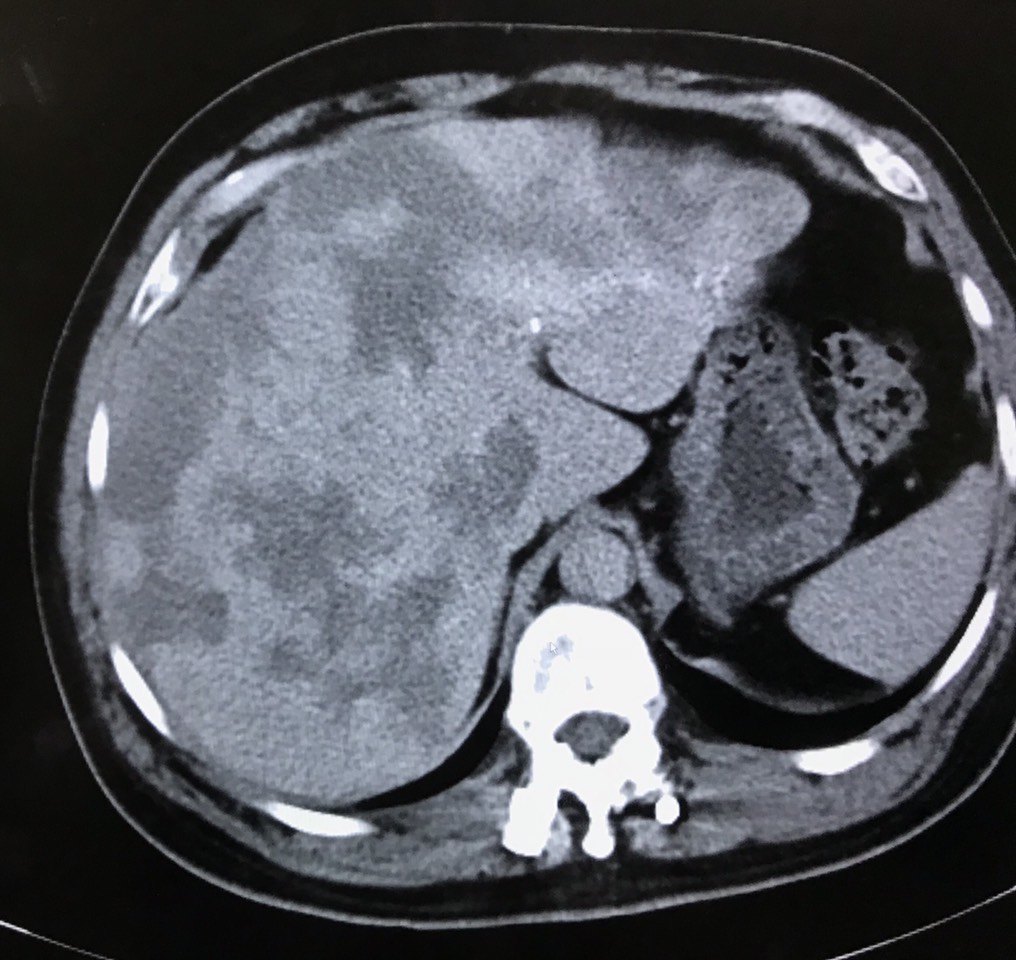

肝血管瘤图片ct

肝海绵状血管瘤的影像诊断

肝脏血管瘤

目前,影像学检查(如b超,ct,mri)是诊断肝血管瘤的主要方法

肝血管瘤